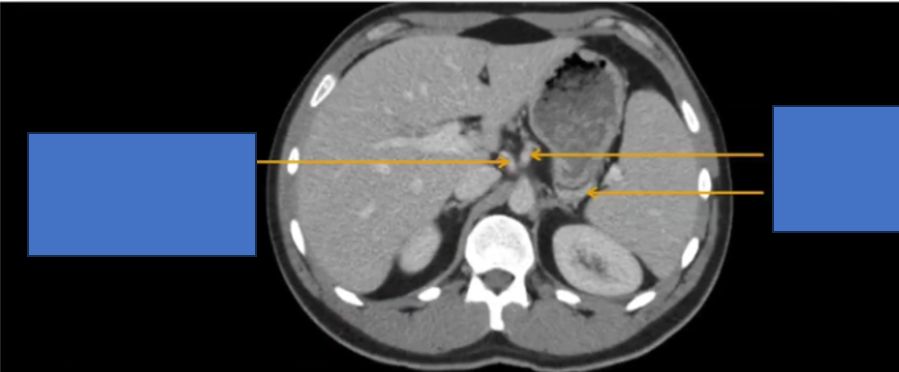

TM gan ở đâu? TM chủ dưới ? ĐM chủ?